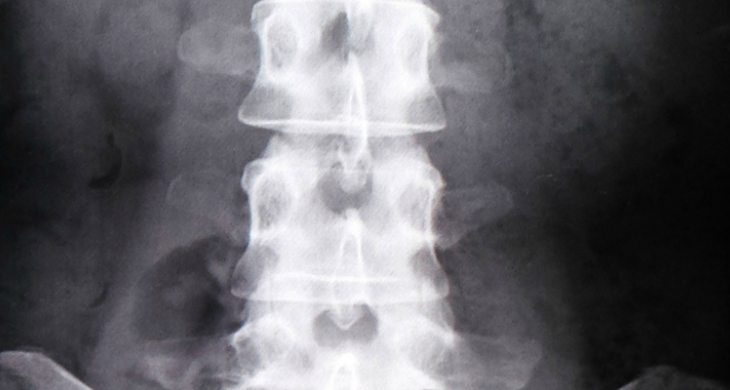

まず最初に、腰痛やヘルニアには特効薬は無く

レントゲン等でも原因の85%は特定でき無いとも言われております。